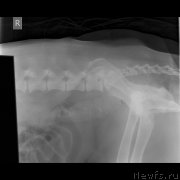

Сделали еще дополнительные снимки.Пес рыдает нон стоп.

Превью фото № 245745

Превью фото № 245746

Превью фото № 245747

По клинической картине и по снимкам - спондилёз поясничного отдела позвоночника. Лечение: первые сутки дексаметазон 4 мг 3 раза /день или преднизолон, можно внутримышечно, и римадил 100мг 3 раза в день.